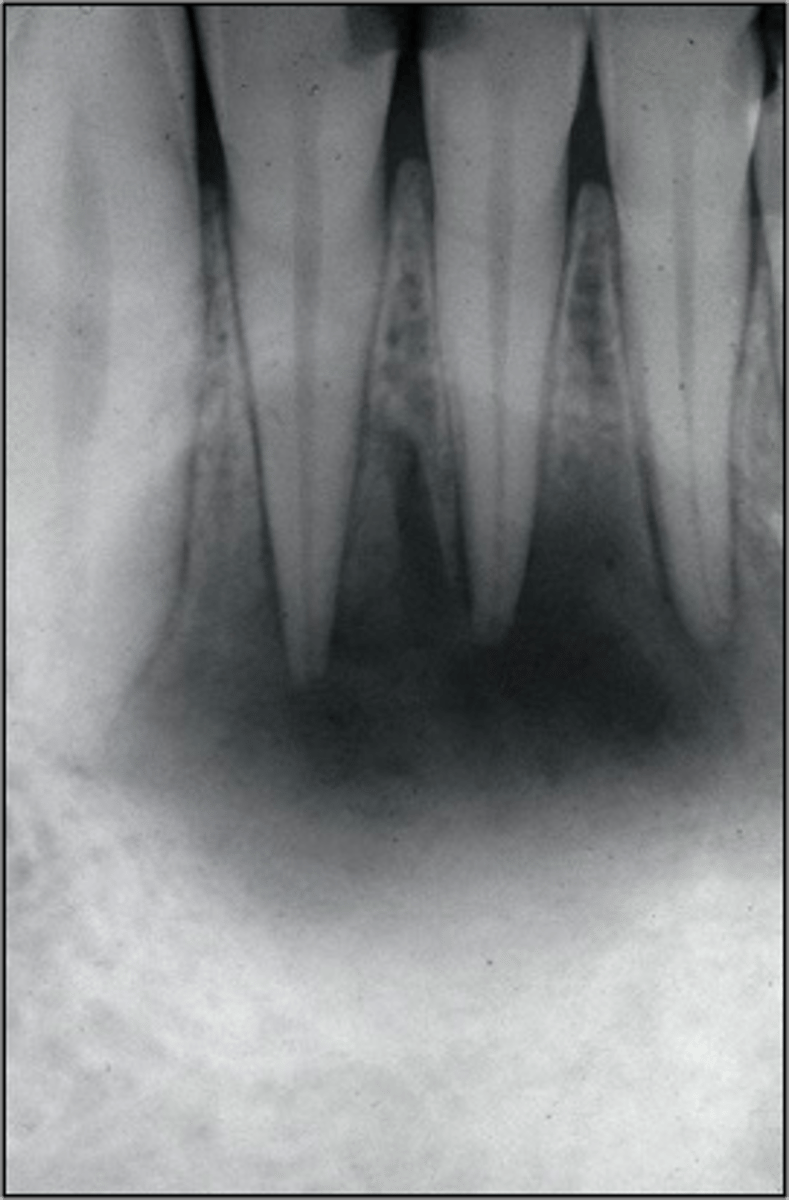

calcified/non-negotiable canal

What is the cause of this apical radiolucency?